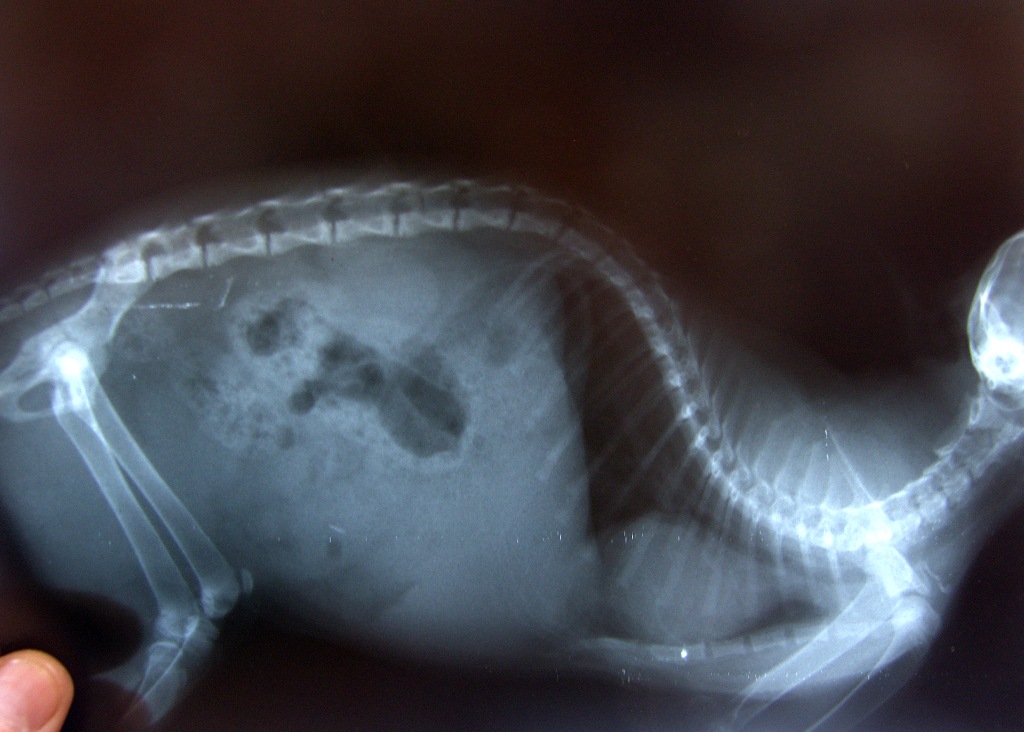

Sur la lignée génétique, la santé des écossais n’est pas considérée comme idéale. Chez les animaux, une déformation des os et un durcissement de la queue peuvent survenir, ainsi que des problèmes de mouvement. La raison de ces problèmes est le pliage d'un pli. Les représentants de la race de chat écossais peuvent souffrir de maladie cardiaque ou de maladie polykystique rénale.